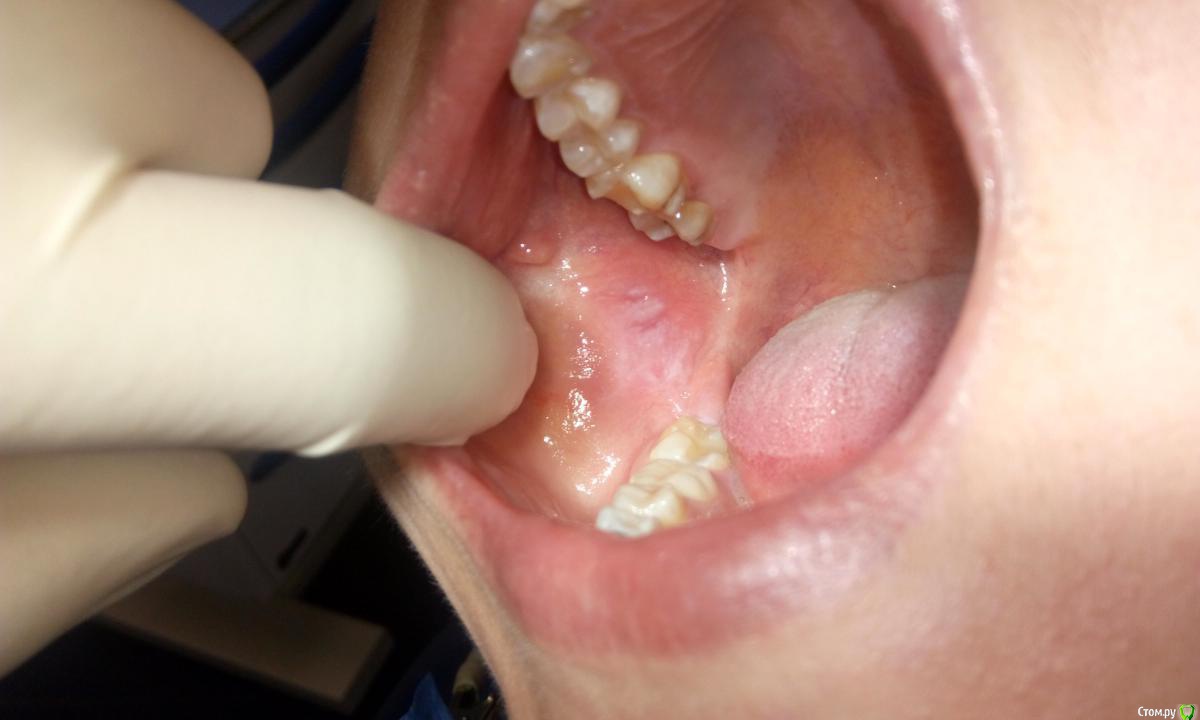

Витторио Орлионе Опубликовано 10 августа, 2016 Поделиться Опубликовано 10 августа, 2016 Здравствуйте, уважаемые коллеги! сегодня обратилась пациентка с жалобами на боли в области щеки справа, усиливающиеся при открывании рта и особенно смешении нижней челюсти в стороны. боль ноющего характера распространяется на всю правую половину щеки и виска. при пальпации самого налёта было не больно, чуть позже разболелось. Налёт не соскребается. пальпация лимфоузлов безболезненная, да и не не нащупываются они. первые признаки появились аж 20 июня в виде белых округлых высыпаний, в том числе и-на предплечье! принимала ацикловир и свечи полиоксидоний, в результате в полости рта сейчас только этот налёт. может быть кто-нибудь сталкивался с подобным?! что это может быть? Ссылка на комментарий

red_butler Опубликовано 10 августа, 2016 Поделиться Опубликовано 10 августа, 2016 похоже на лейкоплакию, а причина болей в другом. ОПГ делали? Ссылка на комментарий

Елена509 Опубликовано 11 августа, 2016 Поделиться Опубликовано 11 августа, 2016 а я все таки за хроническую травму - сидит и покусывает щеку при случае Ссылка на комментарий